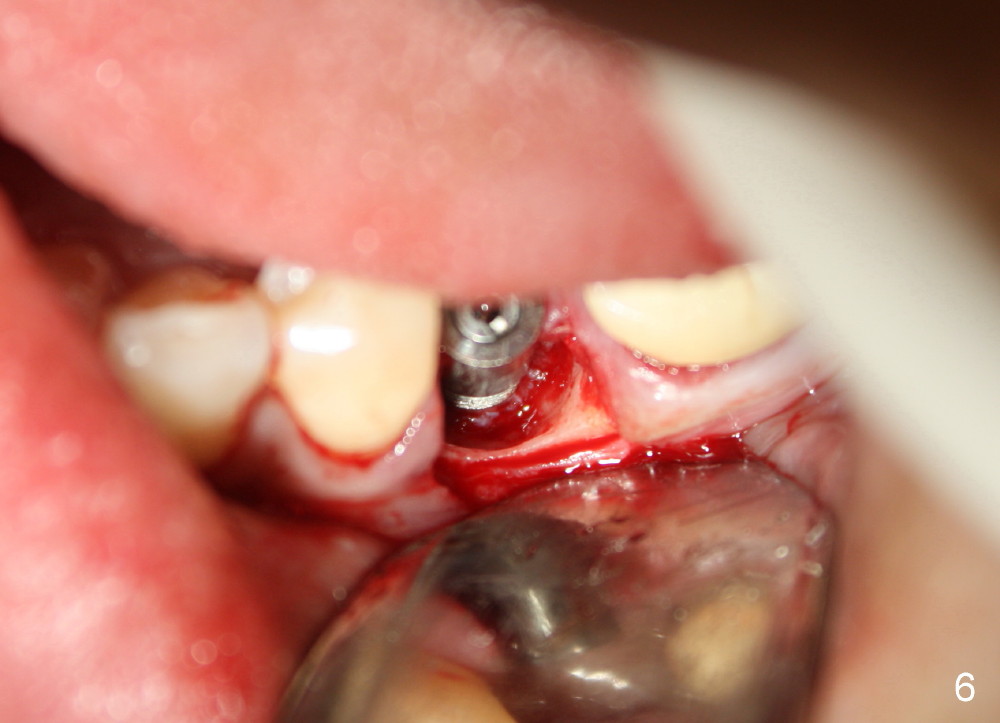

A 44-year-old lady has poor dentition. The tooth #20 has a residual root (Fig.1 R). Immediately after extraction, osteotomy is formed by drills (Fig.2: 3.5x17 mm); a 4.5x17 mm implant is placed (Fig.3 (arrowheads: boundary of the socket)). The patient returns 9 months later with increased radiolucency around the implant (Fig.4) and buccal swelling (Fig.5, asymptomatic). Raising the buccal flap confirms bone loss around the implant (Fig.6). Following debridement, allograft is placed. The source of the infection is unknown.

Four and a half months later, an implant is planned for #18 (Fig.7). The preop PA reveals that there is no bone growth around the implant at the site of #20, although the buccal swelling appears less prominent (Fig.8) than before (Fig.5). Without too much thinking, flap is raised for debridement (Fig.9). Autogenous bone graft is harvested from the site of #18 and placed in the defect area. By the time the surgery is done, the possible source becomes obvious: the periapical infection of the mesial root of #19 (Fig.10 arrowheads from primary infection to secondary one). Since there is also a furca lesion, possibly related to the post (P), the tooth has guarded to poor prognosis.